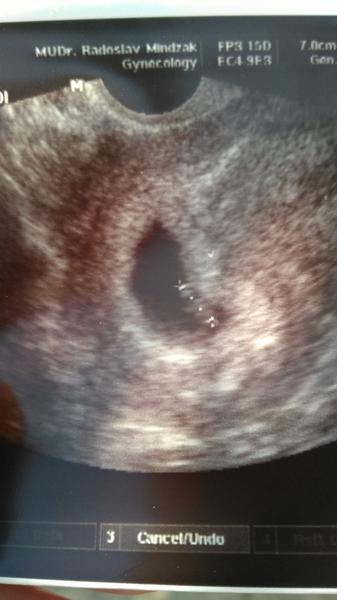

Tak v patek jsem byla u dr a tu je vysledek 7+6

avatar